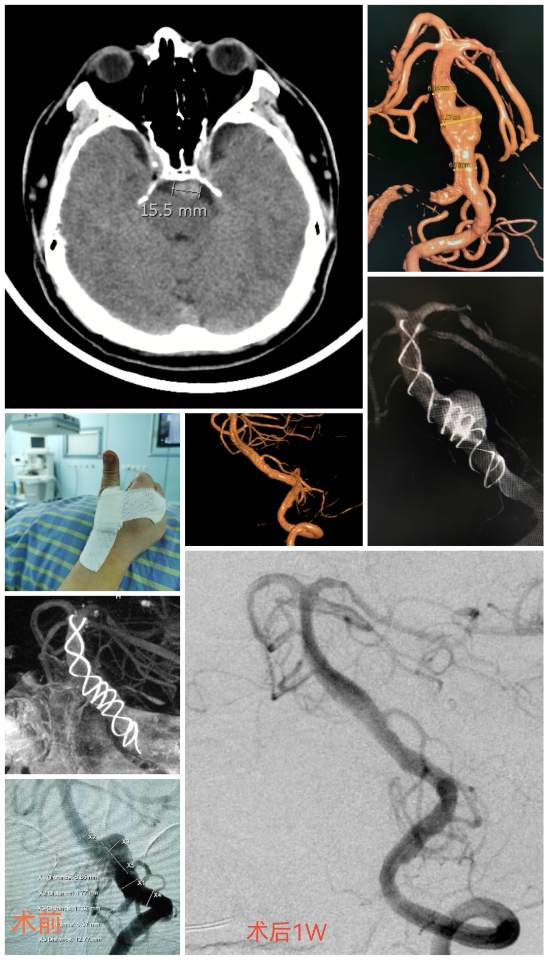

椎基底动脉冗长扩张症,是最棘手最复杂的脑血管病之一。患者从外地千里迢迢(3900余公里,仅高铁41小时)赶来东方医院诊治,期间症状不断加重(图2非真实大小)。术后一周复查:1、右侧肢体肌力明显改善;2、右侧肢体和枕部麻木症状明显改善;3、饮水呛咳缓解;4、共济失调明显改善;5、流涎消失;6、消失的味觉再次恢复。术后一周复查:血管修复良好(图5)。期待患者早日康复,早日奔赴工作岗位,保一方平安。